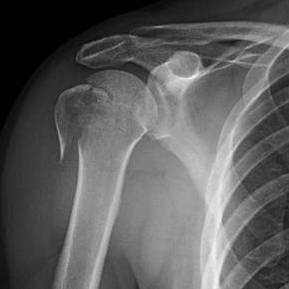

# كسور الطرف العلوي لعظم العضد: نظرة شاملة ## مقدمة تعتبر كسور الطرف العلوي لعظم العضد من الإصابات الشائعة، خاصة بين …

# كسور عظم العضد القريب: الانتشار، الأسباب، التشخيص، والعلاج تُعد كسور عظم العضد القريب من الإصابات الشائعة، خاصةً بين ك…